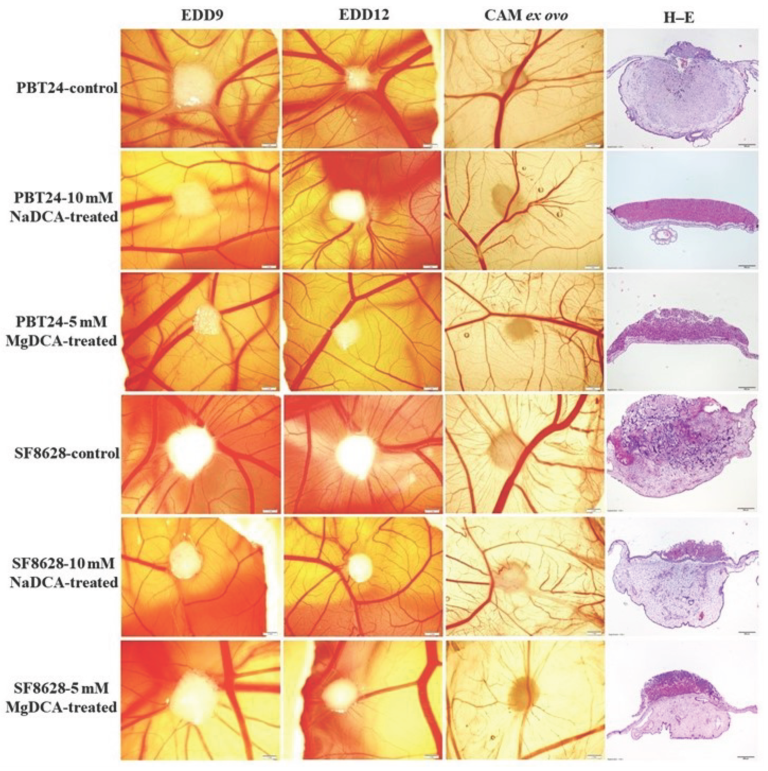

2.1. Stereomicroscopic Findings of Transplanted PBT24 and SF8628 Cell Tumors on CAM